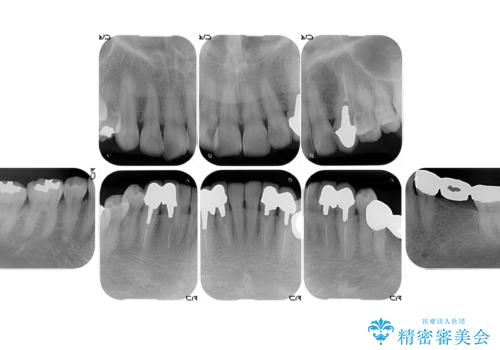

- 前歯の色や形を全体的に綺麗したいといらっしゃった方の症例です。

上顎は左側 4 番目から右側 4 番目までの 8 歯をオールセラミッククラウンで補綴しました。

下顎は左側 4 番目から右側 4 番目までの 8 歯と左下 567 ブリッジをオールセラミッククラウンで補綴し、右下67の銀歯はセラミックインレーによる修復を行いました。